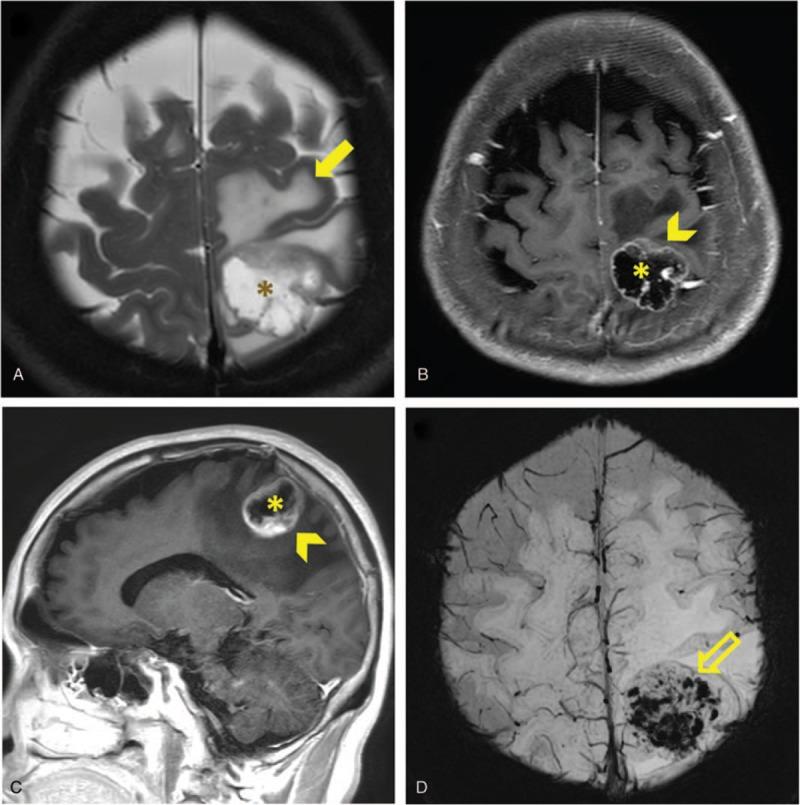

Patients with non-small cell lung cancer (NSCLC) and de novo brain metastasis (BM) have poor prognosis. We aim to investigate the characteristic of brain magnetic resonance (MR) imaging and the association with the treatment response of epidermal growth factor receptor-tyrosine kinase inhibitors (EGFR-TKIs) for lung cancer with BM.EGFR-mutated NSCLC patients with BM from October 2013 to December 2017 in a tertiary referral center were retrospectively analyzed. Patient's age, sex, cell type, EGFR mutation status, treatment, and characteristics of BM were collected. Survival analysis was performed using Kaplan-Meier method. The efficacy of different EGFR-TKIs were also analyzed.Among the 257 eligible patients, 144 patients with Exon 19 deletion or Exon 21 L858R were included for analysis. The erlotinib group had the best progression free survival (PFS) (median PFS 13 months, P = .04). The overall survival (OS) revealed no significant difference between three EGFR-TKI groups. Brain MR imaging features including tumor necrosis, rim enhancement and specific tumor locations (frontal lobe, putamen or cerebellum) were factors associated with poor prognosis. Patients with poor prognostic imaging features, the high-risk group, who received erlotinib had the best PFS (median PFS 12 months, P < .001). However, the OS revealed no significant difference between 3 EGFR-TKI groups. The low risk group patients had similar PFS and OS treated with three different EGFR-TKIs.In NSCLC patients with common EGFR mutation and de novo BM, those with poor prognostic brain MR characteristics, erlotinib provided better PFS than afatinib or gefitinib.

非小细胞肺癌(NSCLC)合并新发脑转移(BM)的患者预后较差。我们旨在研究脑磁共振(MR)成像特征以及其与表皮生长因子受体-酪氨酸激酶抑制剂(EGFR-TKIs)治疗NSCLC合并BM疗效的相关性。对2013年10月至2017年12月在一家三级转诊中心的EGFR突变的NSCLC合并BM患者进行回顾性分析。收集患者的年龄、性别、细胞类型、EGFR突变状态、治疗情况以及BM的特征。采用Kaplan-Meier法进行生存分析。同时分析不同EGFR-TKIs的疗效。在257例符合条件的患者中,纳入144例存在第19外显子缺失或第21外显子L858R突变的患者进行分析。厄洛替尼组的无进展生存期(PFS)最佳(中位PFS为13个月,P = 0.04)。三个EGFR-TKI组之间的总生存期(OS)无显著差异。脑MR成像特征,包括肿瘤坏死、边缘强化以及特定的肿瘤位置(额叶、壳核或小脑)是预后不良的相关因素。具有不良预后成像特征的高危组患者接受厄洛替尼治疗时PFS最佳(中位PFS为12个月,P < 0.001)。然而,三个EGFR-TKI组之间的OS无显著差异。低危组患者接受三种不同的EGFR-TKIs治疗时PFS和OS相似。在具有常见EGFR突变和新发BM的NSCLC患者中,脑MR特征预后不良者,厄洛替尼较阿法替尼或吉非替尼提供更好的PFS。